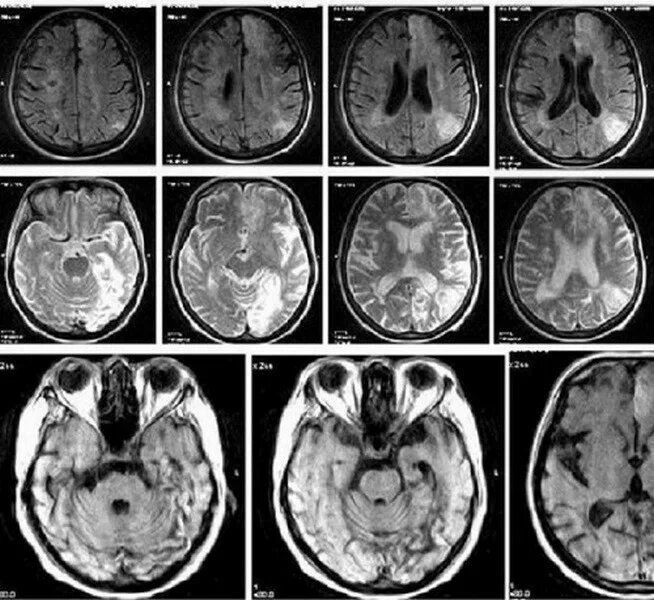

После мрт головного мозга